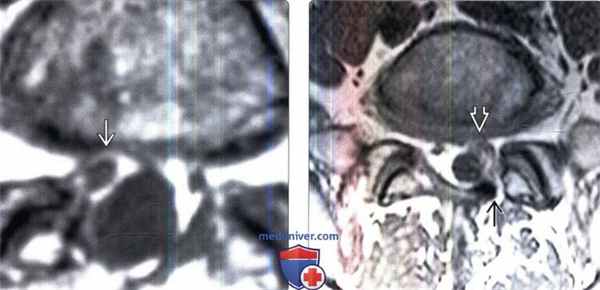

(Слева) Аксиальный срез, Т2-ВИ: небольшой двусторонний постляминэктомический дефект и замещение вентральной эпидуральной клетчатки изоинтенсивной тканью. Признаков объемного воздействия на дуральный мешок или грыжи диска не видно.

(Справа) На аксиальном Т1-ВИ с КУ у этого же пациента отмечается контрастное усиление сигнала мягких тканей в области ляминэктомии и умеренное диффузное усиление тканей в вентральном отделе эпидурального пространства и вокруг корешков.